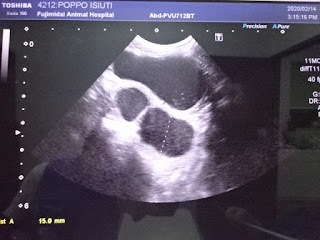

エコーで見ると・・・

上に写っているのが膀胱で

その下に写っているのが子宮・・・

膀胱は異常ありませんでしたが・・・

子宮に水が溜まっているそうです

子宮水腫です

子宮は今3センチぐらいに膨らんでいるけれど

1年ぐらい前のエコーを見るとこの時は異常がないから

急に膨らんだ感じではなく、徐々に溜まってきたみたいで